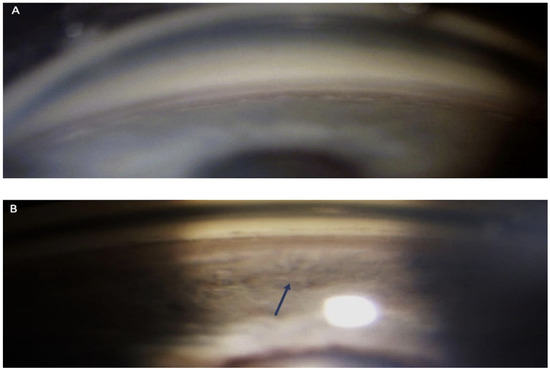

3. Case Report